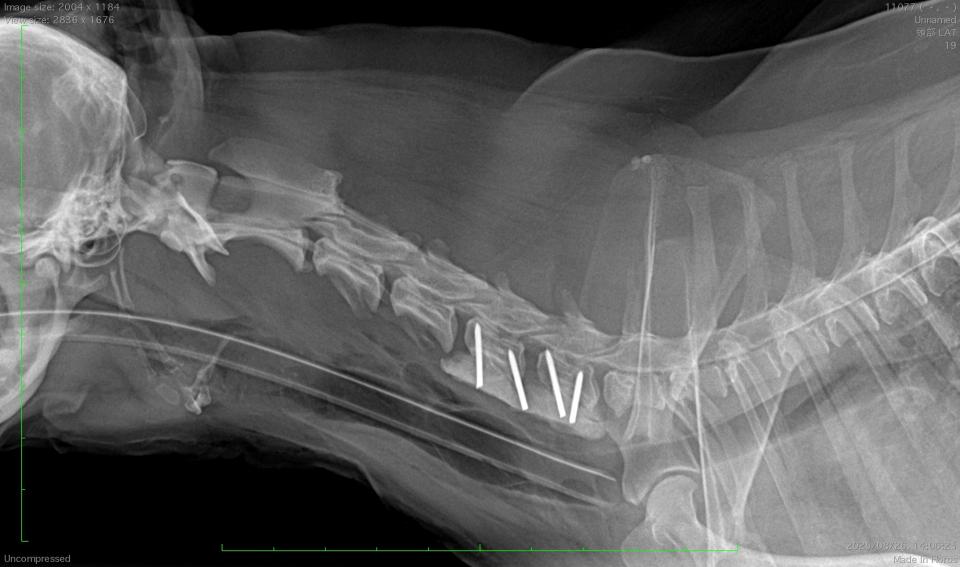

C5-6椎間に対するベントラルスロット術および椎体固定術を実施しました。

術中に摘出した椎間板の線維輪は変性して疎になっており、正常犬と比較して脆弱化していました。

術後3日目には自力歩行が可能でした。